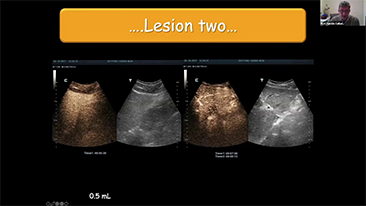

??? ?? ??? ?? ???? ? ??? ?? ??? ?? ??? ??? ??? ???. ???? ??? UWN+ ?? ?? ??? ?? MI??? ??? ??? ?? ?? ??? ?? ?? ?? ???, ?? ?? ?? ???? ??? ? ????.